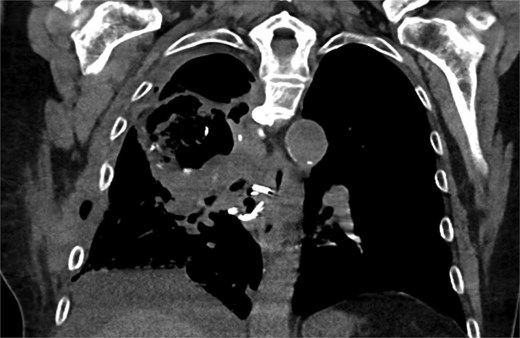

Six weeks postoperatively, he presented to the emergency room with several weeks of chest pain, dyspnea, and fatigue. A non-contrast computed tomography (CT) scan revealed a large cavitary mass of the posterior right upper lobe hilum, associated with fluid collections in the adjacent chest wall and loculated pleural effusion, raising concern for cavitary abscess (Fig. 1). He was admitted to the hospital floor and started on broad-spectrum intravenous antibiotics.

Coronal CT showing large cavitary lesion in the right upper lobe measuring 10.0 × 6.0 cm, loculated right pleural effusion, complex chest wall fluid collection.